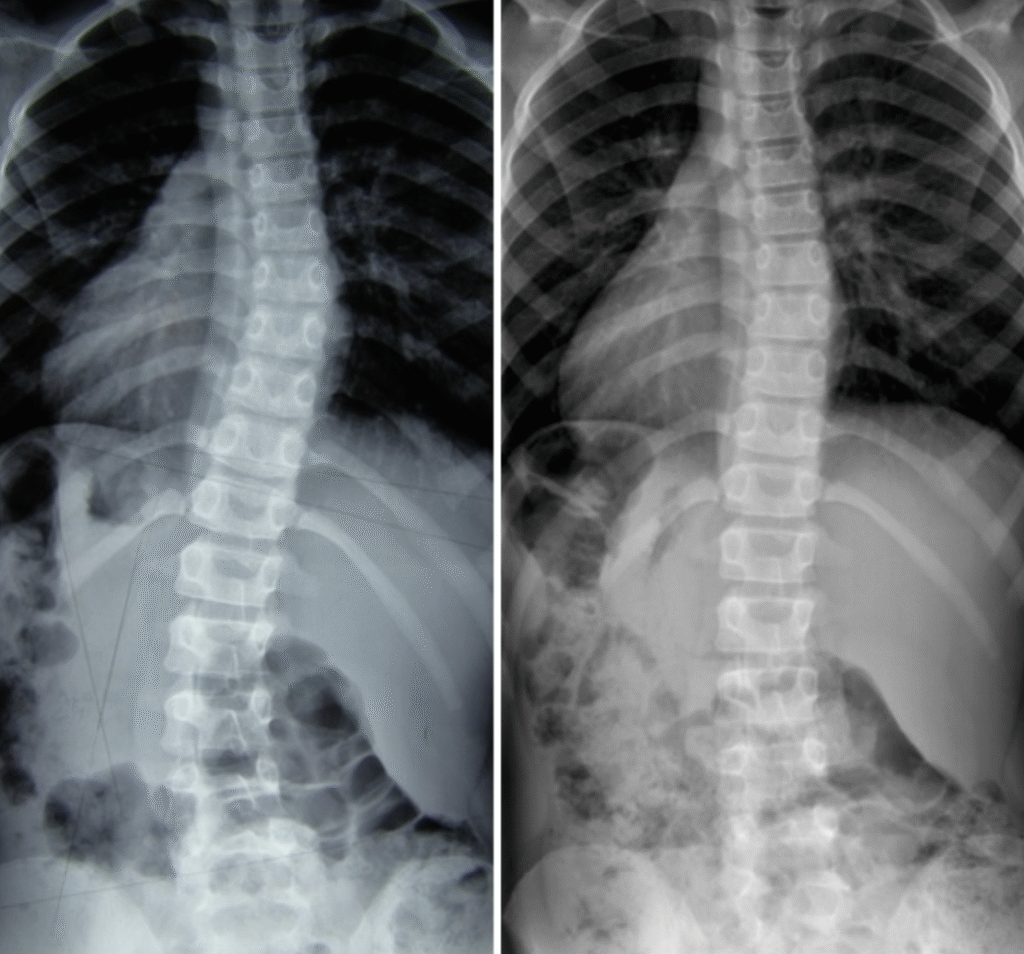

Martyna – 10 lat

Terapia prowadzona w okresie 03.10.2016 – 02.01.2017 (20 zabiegów) Częstotliwość zajęć – 2 x tydz. Po skończonej terapii dziecko było pod kontrolą naszego ośrodka. W lutym 2019 zrobiono zdjęcie RTG, które nie wykazało skrzywienia kręgosłupa.